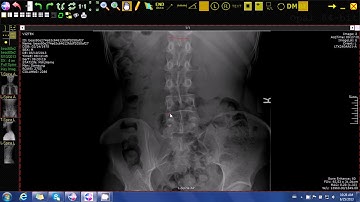

20 Multiple Cobb Angles Tool